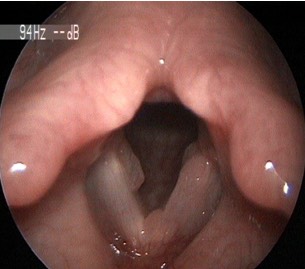

2654. Данная ларингеальная картина характеризует